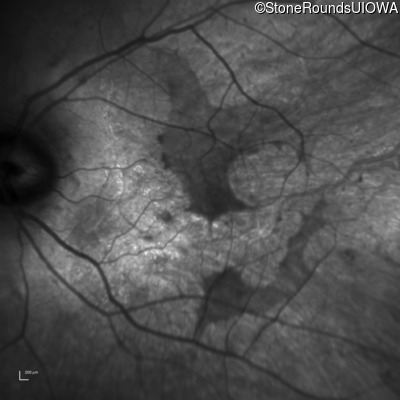

Infrared Fundus Photograph - Right - 20/50 sc

Exemplar

Infrared Fundus Photograph - Left - 20/40 sc